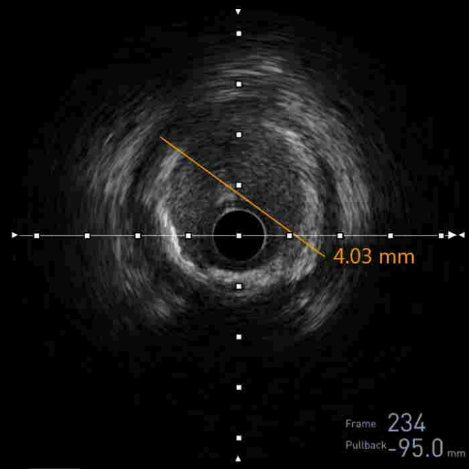

IVUS测得LAD远端参考直径(media-media) = 3.65mm

IVUS测得LAD近端参考直径(media-media) = 4.03mm

IVUS指导支架植入位置及尺寸

远端参考直径3.65mm

Distal to Proximal 17.61mm

近端参考直径4.03mm